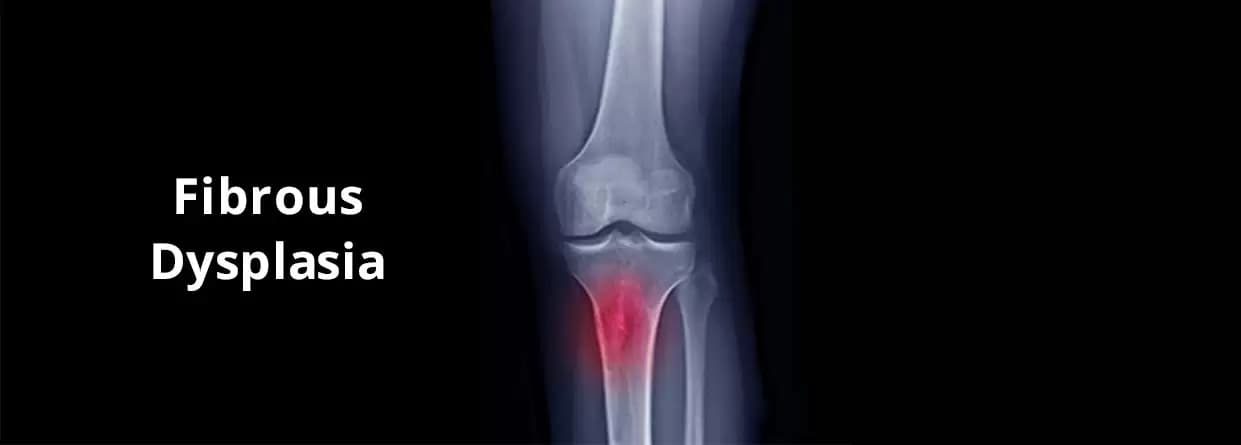

Fibrous dysplasia as the name suggests refers to the rare medical condition where our bodies replace healthy bones with fibrous bone-like tissues. This can increase the risk of injuries and fractures resulting in nerve compression and other complications. Fibrous dysplasia can occur in any individual at any age.

Fibrous dysplasia as the name suggests refers to the rare medical condition where our bodies replace healthy bones with fibrous bone-like tissues. This can increase the risk of injuries and fractures resulting in nerve compression and other complications. Fibrous dysplasia can occur in any individual at any age. Depending on the patient's medical health, fibrous dysplasia symptoms can be mild to severe.